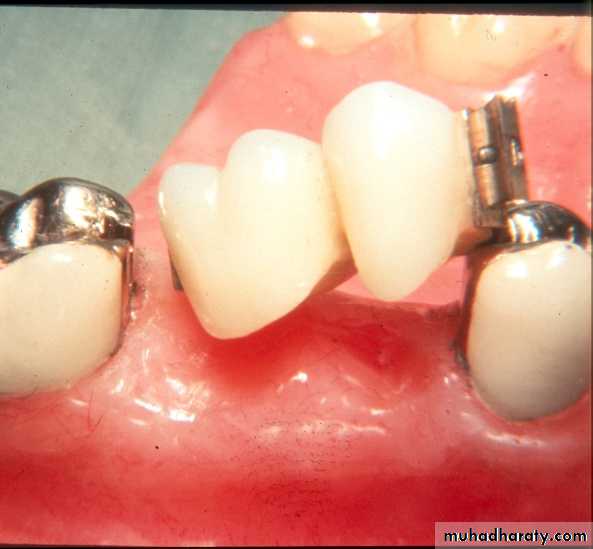

Intracoronal Attachments-Incorporated entirely within the contour

of the crown.-Non-resilient. -Usually indicated in bounded cases.

Intracoronal Attachments versus clasp retainersADVANTAGES

** Esthetics: elimination of clasps arms.

** Retention unaffected by crown contour.

** Reduced bulk of the prosthesis: fits within the contour of a tooth crown yet serves the functions of an occlusal rest, retentive clasp arm and bracing arm.

** More Hygienic: elimination of food stagnation.

DISADVANTAGE

** Extensive preparation of the abutment teeth.LIMITATIONS

** Require a minimum of 4mm vertical space & adequate BL width.